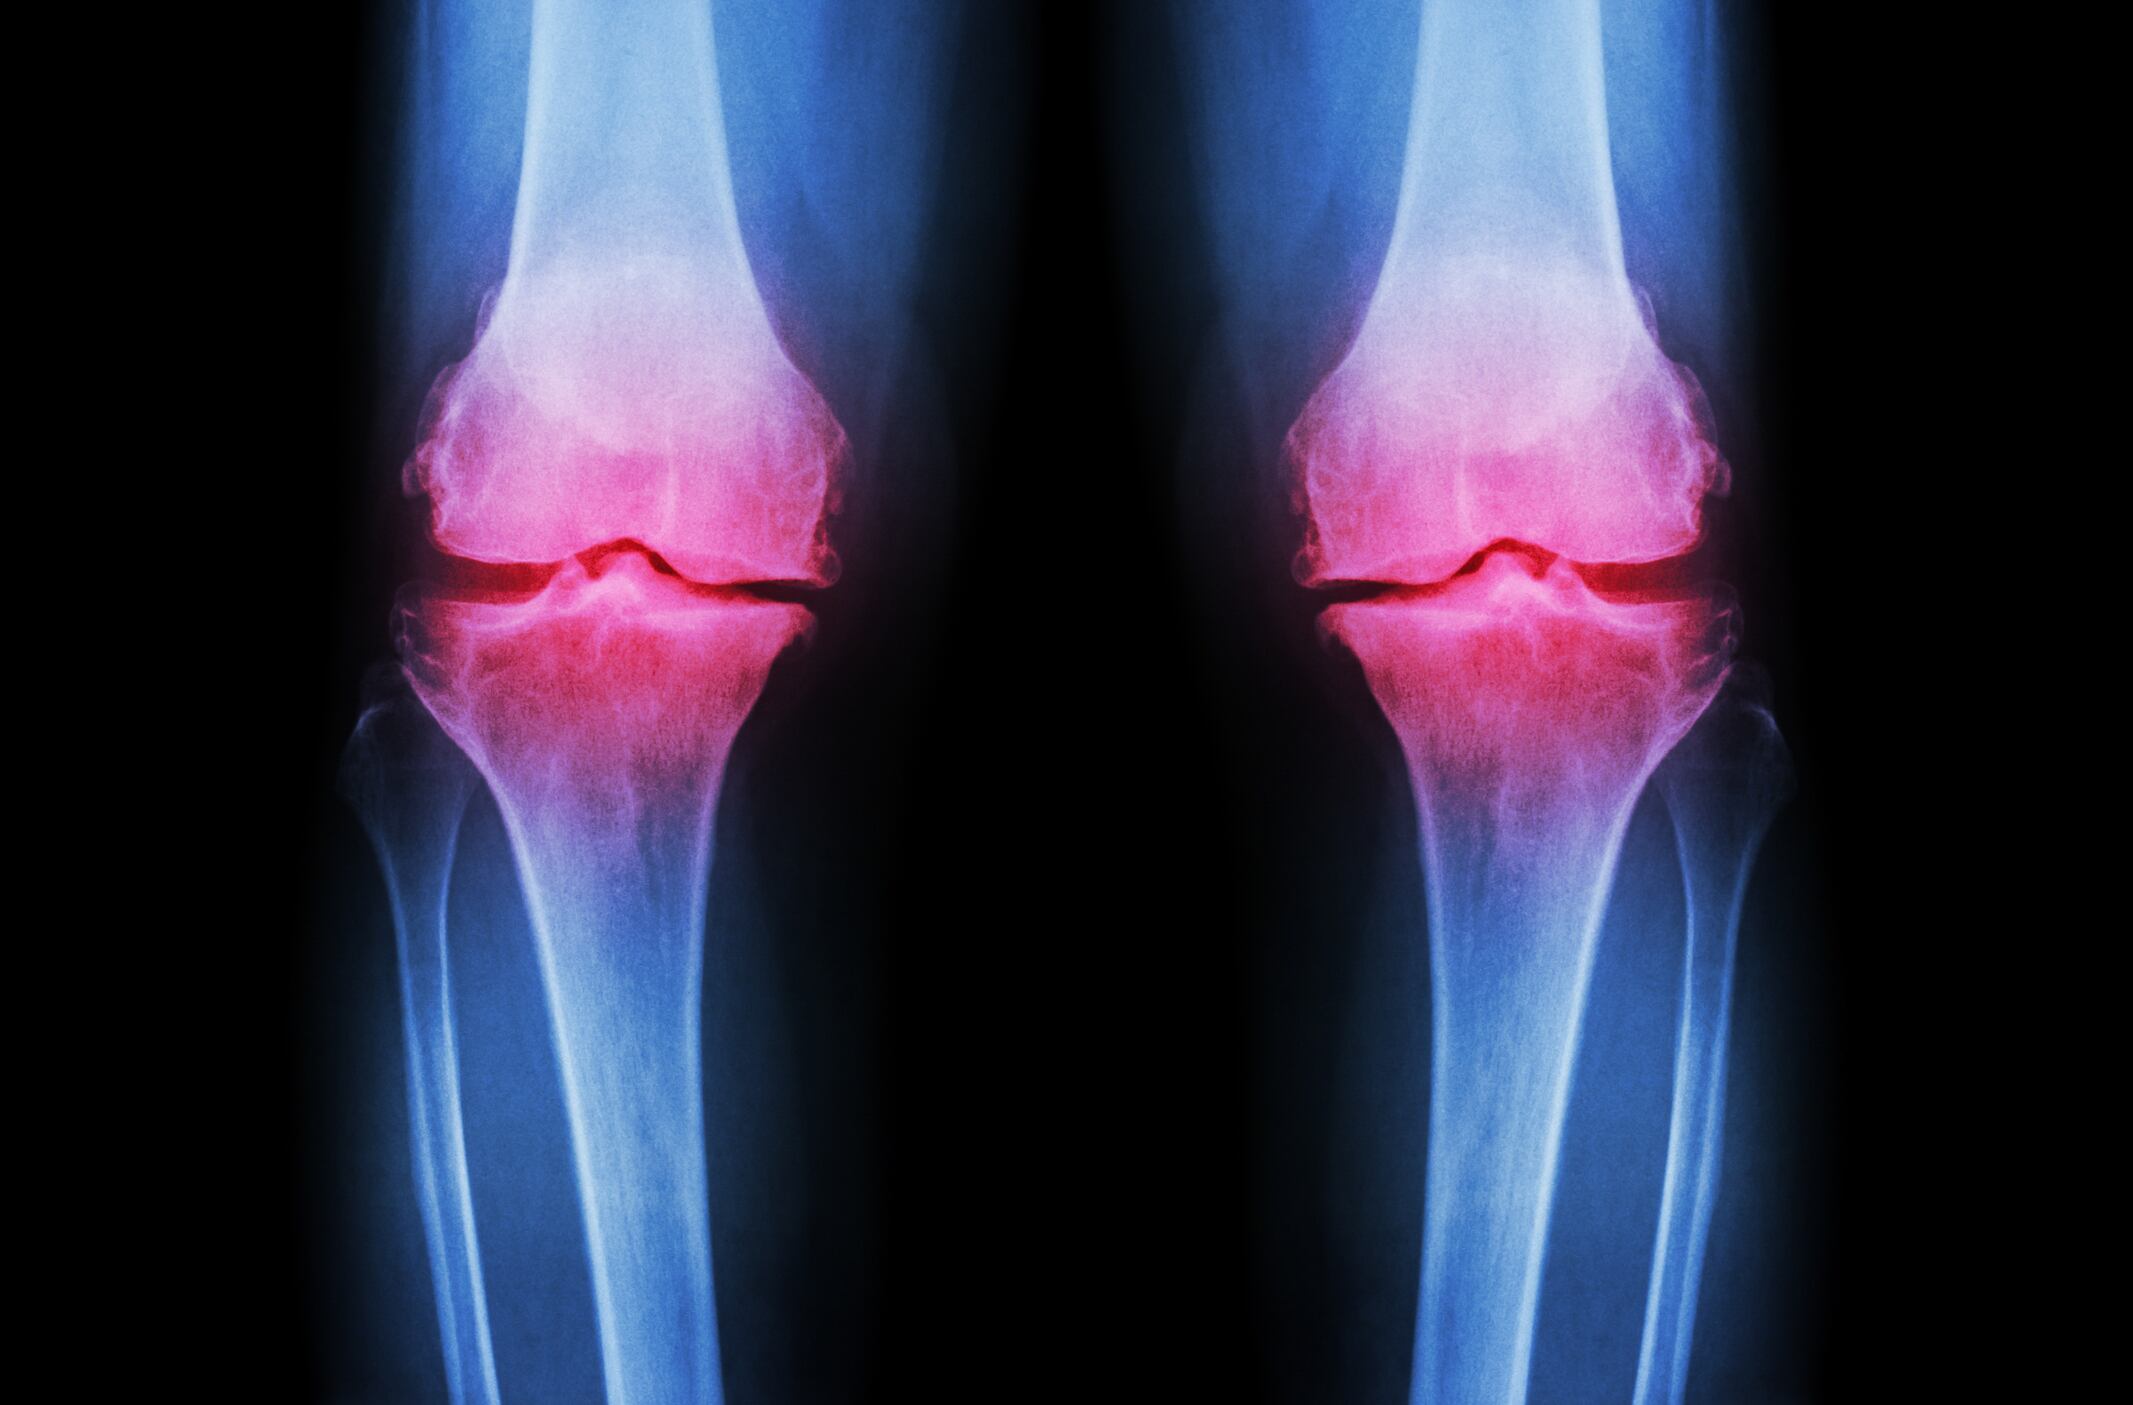

A gastroresistant supplement formulation containing a combination of Boswellia serrata and bromelain may improve the quality of life (QoL) in people with QoL of patients suffering from osteoarthritis (OA), says a new pilot study.